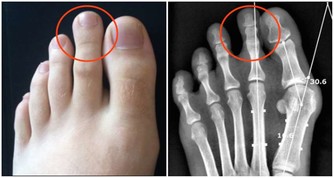

1。便秘的問題

便秘的人肛門排氣較多,而且往往有臭味,因為排泄不暢,糞便在結腸中長期堆積,腐敗菌分解為產氣。